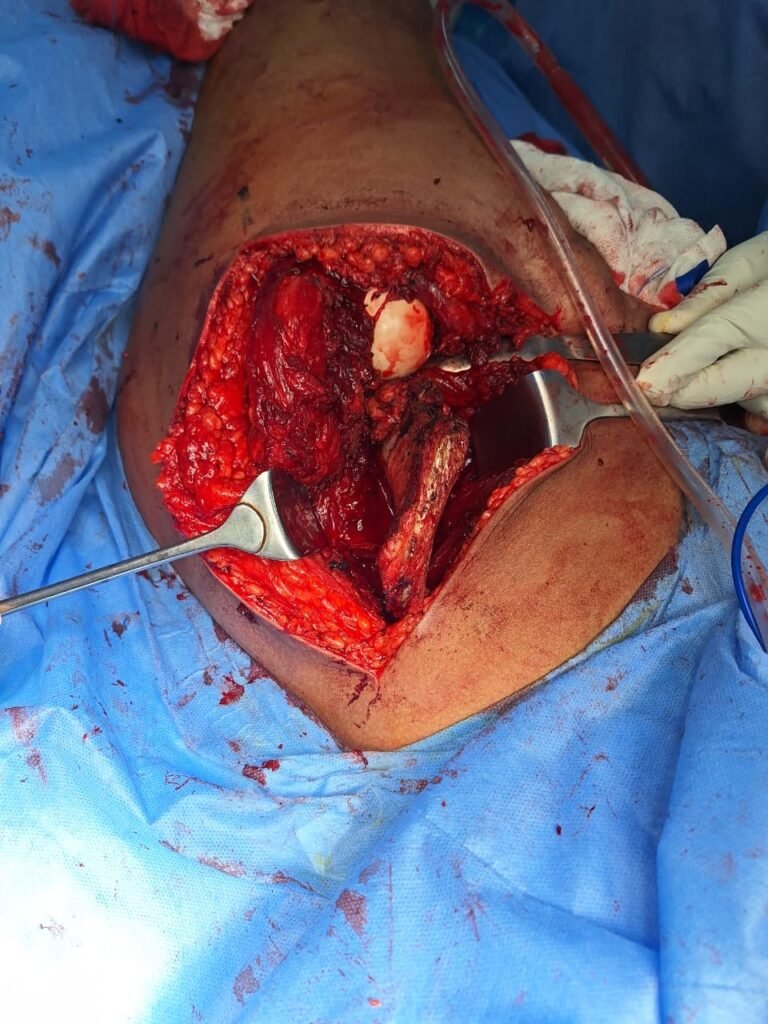

خلال جراحة توسيع الفجوة، يقوم الجراح بقطع قطعة من العظم من الساق ويقرب جوانب الفتحة لإغلاق المسافة.

في بعض الحالات، يفتح الجراح قسمًا من العظم بدلاً من إغلاقه. يُسمى هذا الإجراء شق توسيع الفجوة. في بعض الأحيان يتم استخدام رقعة عظمية وشريحة و مسامير للمحافظة على المسافة بين أطراف الفجوة التي تم توسيعها.

يوجد العديد من الخيارات لتثبيت على الشق العظمي و توسيع الركبة في مكانه حتي تمام الالتئام ، و يمكنك مناقشة هذه الاختيارات مع دكتور العظام المتخصص في الركبة. يتضمن ذلك مسامير معدنية شريحة أو رقعة عظمية للحفاظ على العظام في مكانه أثناء الشفاء. عادة ما تستغرق جراحة توسيع الركبة ساعة إلى ساعتين.